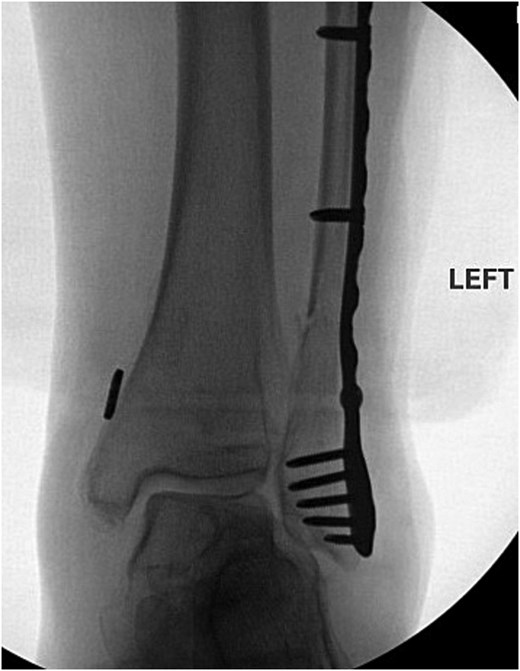

The patient is a 61-year-old female with a past medical history of idiopathic neuropathy with balance disorder, morbid obesity, and vitamin D deficiency presented to the clinic after she sustained an atraumatic injury to the right ankle. Notably, the patient required surgical treatment 2 years prior for an atraumatic left Weber C lateral malleolus fracture with Stage 3 posterior tibialis tendonitis and pes planus deformity (Fig. 1). Radiographs obtained at the time of injury to her right ankle showed no acute osseous abnormalities or dislocations and she was given a tall controlled ankle motion (CAM) boot. Magnetic resonance imaging (MRI) was later obtained demonstrating an acute Weber C fibular fracture with partial-thickness tearing of the syndesmotic membrane (Fig. 2). She was diagnosed with a right ankle lateral malleolus Weber C stress fracture. Patient initially elected for nonsurgical treatment but after a week with stable pain with limited function, she elected for surgical intervention a week after injury.

Anterior–posterior post-operative X-ray demonstrating fixation of left Weber C fibular fracture.